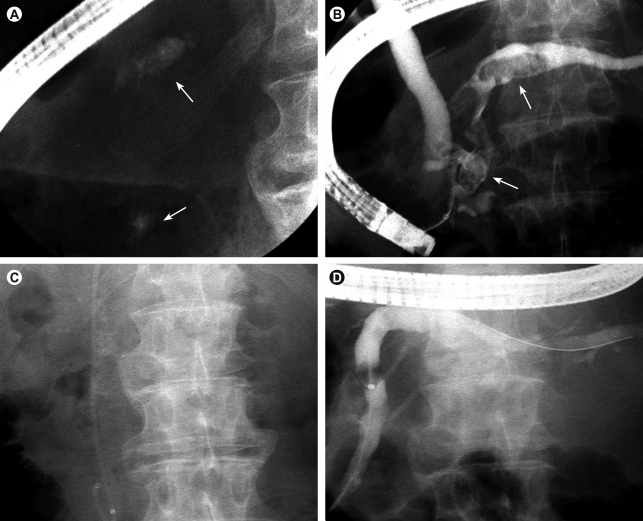

Figure 2

Extracorporeal shock wave lithotripsy (ESWL) to facilitate removal of pancreatic duct stones. (A) Two pancreatic calcifications (arrows) are seen on the plain film. (B) Two filling defects (arrows) were observed in the main pancreatic duct, which were difficult to remove due to their large size. (C) Radiopaque stones seen alongside the pancreatic stent were fragmented successfully after ESWL. (D) Fragmented pancreatic stones are removed by sweeping using a retrieval balloon.